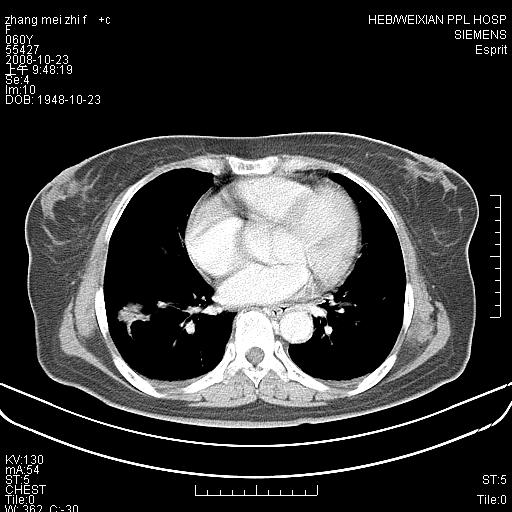

体检发现肺部肿块,现无不适。五年前曾有过哮喘病史。

强化扫描后病灶几乎无增强,强化后的病灶看起来密度虽高,是我为了清晰改变了窗宽窗位。(有点弄巧呈拙)

先对现有的图象资料谈几点看法:病变位于右肺下叶前基底段,上部呈类圆形改变,分叶及毛刺征象不明显,下部呈不规则气腔改变,近肺门侧可见与一粗大血管相连,考虑为引流静脉影.其他肺叶相对正常所见.分析:该病灶良恶性均有可能.(现有资料来说).强化及穿刺活检有助鉴别.

考虑右肺下叶前基底段周围型肺癌可能性大。

右肺下叶前基底段占位性病变,不排除周围型肺癌可能,尽快手术为妙。